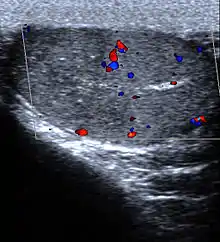

- Lung: Pulmonary infarction or lung infarction